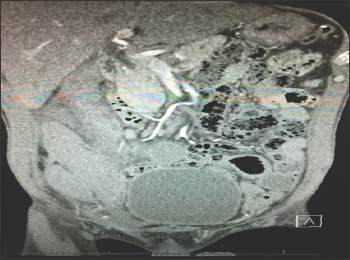

Figure 1: Fluorescent MSC in injured area of rat's cerebral cortex (trauma contours are to the right).

Figure 1 shows diffuse distribution of fluorescent formations in sensorimotor brain area. The picture is associated with the Milky Way at night. So, Figure 1 demonstrates vast distribution of perineurally implanted MSC in the area of local brain trauma. MSC are considered [3,4] to excrete various neurotrophic factors which activate reparative potential of endogenous stem cells. Also, neurotrophic factors from MSC inhibit processes of apoptosis and necrosis in the cells of damaged brain regions [4,5]. Another point of view highlights functional role of MSC in creation of new neural networks from implanted neuron-like cells. Dynamics of synaptic transmission in neural network affects variability of response of neural network elements [6]. At this time functional state of interaction between cells in neural network which are either in excitability or refractivity phase is the key factor for neuron's response both in neural network and separate neurons [7,8]. Series of in vitro experiments was performed to answer these questions. Figure 2 shows one of the results.